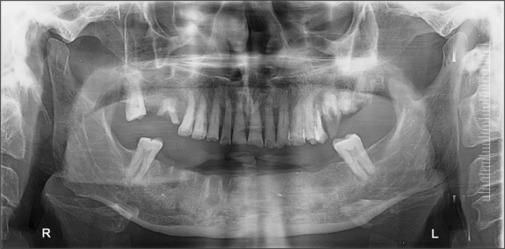

The sialolith is a calcified mass resulting from the crystallization of salivary solute made up of calcium phosphates such as hydroxyapatite and octacalcium phosphate with yellowish discoloration and different shapes and sizes in the range of 1-2 cm normally, while occurrence of large sialolithiasis is rare, with literature showing sizes from 3.5 cm to 7 cm noted till date. About 80% of sialolithiasis occurs in submandibular glands and 20% in parotid gland and <1% is seen with sublingual gland. For small sialolithiasis and for superficially located sialolithiasis at ductal regions, conservative management is performed. However, for larger sialolithiasis, surgical management is mandatory which includes various methods such as transoral sialolithotomy, laser techniques, and sialendoscopy-assisted techniques. Complete excision of salivary gland is recommended for large, multiple, and recurrent cases of sialolith. In the present study, we have presented the unusual-sized rare case of salivary gland stone found in submandibular salivary gland and not in ductal region which was mimicking an osteoma on OPG and discuss the review of literature. This giant sialolith was managed with extraoral submandibular approach followed by TOTO removal of the sialolith which measured about 38 g in weight and 28 mm in size. Present sialolith was the rarest till date with heavyweight of about 38 g and 28 mm in size. Even the conventional method is sufficient to excise the sialolith when other modalities are not available. Chronic sialolith is common in old male patients and shows positive correlation with chronic smoking.

涎石是由唾液溶质结晶形成的钙化团块,其主要成分是磷酸钙,如羟基磷灰石和磷酸八钙,通常呈淡黄色,形状和大小各异,一般在1 - 2厘米范围内,而大涎石病的发生较为罕见,文献记载至今发现的最大尺寸为3.5厘米至7厘米。约80%的涎石病发生于下颌下腺,20%发生于腮腺,舌下腺发病<1%。对于小涎石病以及导管区域浅表性涎石病,采取保守治疗。然而,对于较大的涎石病,则必须进行手术治疗,包括经口涎石切除术、激光技术和涎腺内镜辅助技术等多种方法。对于大的、多发的和复发性涎石病例,建议完整切除涎腺。在本研究中,我们报告了一例罕见的、尺寸异常的涎腺结石病例,该结石位于下颌下涎腺而非导管区域,在全景片上类似骨瘤,并对相关文献进行了综述。该巨大涎石采用口外下颌下入路,随后通过TOTO法取出,涎石重量约38克,尺寸为28毫米。目前的涎石是迄今为止最罕见的,重量约38克,尺寸为28毫米。当没有其他方法可用时,传统方法也足以切除涎石。慢性涎石在老年男性患者中较为常见,且与长期吸烟呈正相关。